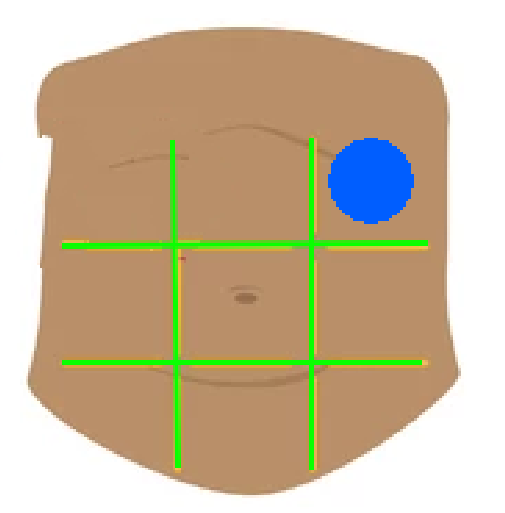

Right hypochondriac region

Left hypochondriac region

Epigastric region

Right lumbar region

Left lumbar region

Umbilical region

Right inguinal region

Left inguinal region

Hypogastric regions